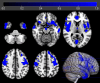

Results: sALS patients showed significant relative hypometabolism in bilateral fronto-temporo-occipital cortex and right insula as compared with FUS-ALS. After adjusting for age, the relative hypometabolism remained in the bilateral precentral gyrus and in the right middle and inferior temporal gyrus. As compared with HC, FUS patients displayed a significant relative hypermetabolism in the pontobulbar region and right cerebellar tonsil, dentate nucleus, and uvula, while sALS showed relative hypometabolism in bilateral frontal and occipital cortices and in left temporal and parietal regions.

Interpretation: Patients with FUS-ALS show relative preservation of motor cortex metabolism compared with those with sALS, possibly reflecting the prevalence of lower motor neuron impairment in their phenotype. Prospective studies are necessary to investigate the possible role of 2-[18F]FDG-PET as a biomarker to track disease spreading in clinical trials. ANN NEUROL 2025;97:1134-1143.